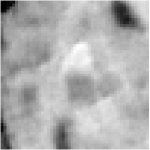

All the experiments are implemented on a Windows workstation with Intel Core i9 CPU at 3.3GHz and an Nvidia GTX-1080Ti GPU with 11GB of graphics card memory via TensorFlow Abadi et al. (2016). The parameters in the proposed network are initialized by using Xavier initialization Glorot and Bengio (2010). We trained the meta-learning network with four tasks synergistically associated with four different CS ratios: 10%, 20%, 30%, and 40%, and test the well-trained model on the testing dataset with the same masks of these four ratios. We have 300 training data for each CS ratio, which amount to total of 1200 images in the training dataset. The results for and MR reconstructions are shown in Tables 5.4 and 5.4 respectively. The associated reconstructed images are displayed in Figures 1 and 3. We also test the well-trained meta-learning model on unseen tasks with radio masks for skewed ratios: 15%, 25%, 35%, and random Cartesian masks with ratios 10%, 20%, 30% and 40%. The task-specific parameter for the unseen tasks are retrained for different masks with different sampling ratios individually with fixed task-invariant parameters . In this experiments, we only need to learn for three skewed CS ratios with radio mask and four regular CS ratios with Cartesian masks. The experimental training proceed on less data and iterations, where we performed on 100 MR images with 50 epochs. For example, for reconstructing MR images with CS ratio 15% radio mask, we fix the parameter and retrain the task-specific parameter on 100 raw data with 50 epochs, then test with renewed on our testing data set with raw measurement that sampled from radio mask with CS ratio 15%. The results associated with radio masks are shown in Table 5.4 and 5.4, Figure 2 and 4 for and images respectively. The results associated with Cartesian masks are list in Table 5.4 and reconstructed images are displayed in Figure 5.

Qualitative comparison between conventional and Meta-learning methods are shown in Figure 1 and 3, which display the reconstructed MR images of the same slice for T1 and T2 respectively, we label the zoomed-in details of HGG in the red boxes. We observe the evidence that conventional learning is more blurry and lost sharp edges, especially in lower CS ratios. From the point-wise error map, we find meta-learning has the ability to reduce noises especially in some detailed and complicated regions comparing to conventional learning.

In this section, we test the generalizability of the proposed model that tests on unseen tasks. We fix the well-trained task-invariant parameter and only train for sampling ratios 15%, 25% and 35% with radio masks and sampling ratios 10%, 20%, 30% and 40% with Cartesian masks. In this experiment, we only used 100 training data for each CS ratio and apply a total of 50 epochs. The averaged evaluation values and standard deviations are listed in Table 5.4 and 5.4 for reconstructed T1 and T2 brain images respectively that proceed with radio masks, and Table 5.4 shows the qualitative performance for reconstructed T2 brain image that applied random Cartesian sampling masks. In T1 image reconstruction results, meta-learning improved 1.6921 dB in PSNR for 15% CS ratio, 1.6608 dB for 25% CS ratio, and 0.5764 dB for 35% comparing to the conventional method, which in the tendency that the level of reconstruction quality for lower CS ratios improved more than higher CS ratios. A similar trend happens in T2 reconstruction results with different sampling masks. The qualitative comparisons are illustrated in Figure 2, 4 and 5 for T1 and T2 images tested in skewed CS ratios in radio masks, and T2 images tested in Cartesian masks with regular CS ratios respectively. In the experiments that conducted with radio masks, meta-learning is superior to conventional learning especially at CS ratio 15%, one can observe that the detailed region in red boxes keeps edges and is more close to the true image, while conventional method reconstructions are hazier and lost details in some complicated tissue. The point-wise error map also indicates that Meta-learning has the ability to suppress noises.